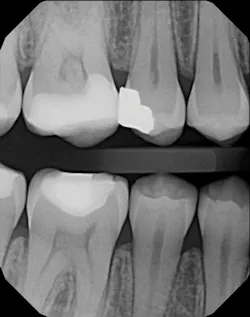

DEXIS CariVu image

In my practice, a caries detection device provides an excellent adjunct to radiographs. We use a device (CariVu, DEXIS) with near-infrared transillumination technology to produce images that look similar to x-rays. For example, a potential Class II lesion may appear as a suspicious area on a radiograph, but it will show as a much larger lesion on a CariVu image. Since this modality does not emit ionizing radiation, it is appreciated by radiation-averse patients, including parents who wish to avoid x-ray use on their children and patients whose medical history precludes x-rays. In my office, patients who refuse to have radiographs sign an informed refusal, and then we take a CariVu evaluation. If we notice an area that needs treatment, then we request to take a radiograph of that to corroborate and find more information.